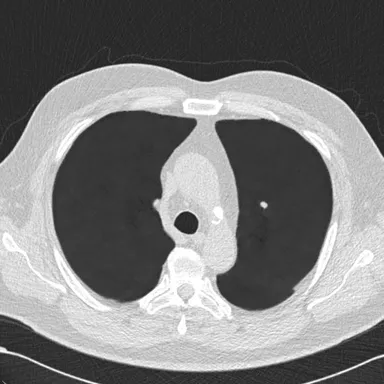

・胸部CT肺血管透過処理システム/ClearRead CT-VS※2

胸部CT画像の肺血管を透過した画像を生成し、肺結節や異常陰影の視認性を向上させる。

・「ClearRead CT-VS」:胸部CT肺血管透過処理システム

- 肺組織の視認性を大きく向上

- 肺血管透過処理画像を生成

- 胸部CT画像上の病変の見落とし防止、気づきの促進

- 国内外あらゆる胸部CT装置で撮影された画像に対応